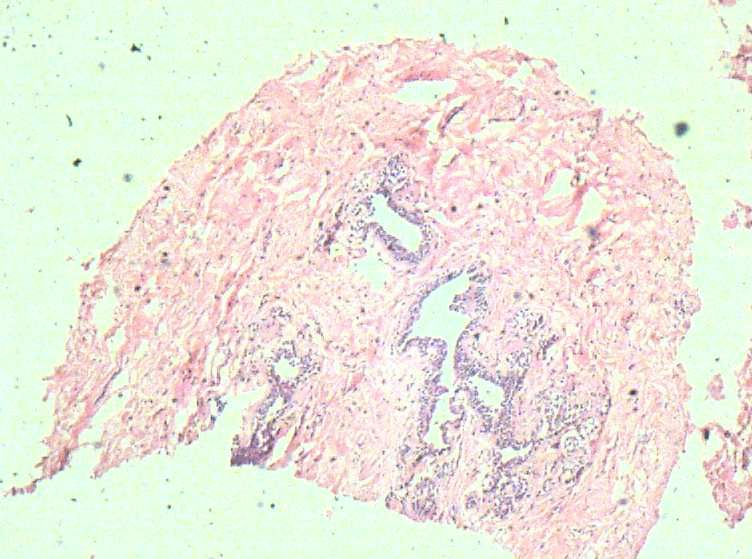

B3774乳腺积乳性包块?

女41岁,左腺包块。肉眼:不整形囊壁样组织,大小2*1.6*0.3CM,壁厚0.1—0.3,未触及结节,未见出血及坏死。

标签:乳腺纤维囊性增生症

似乎有导管扩张、慢性炎细胞浸润、大汗腺化生、普通型导管增生等病变,没有看到囊壁内衬上皮或囊壁结构。

乳腺腺病伴普通型导管增生